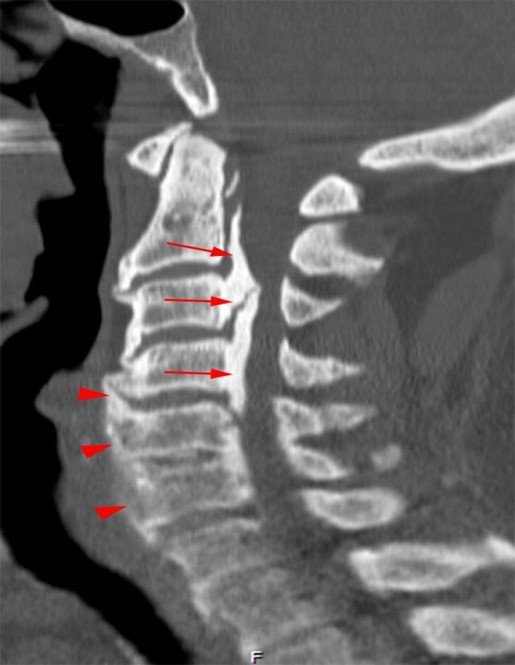

A 64-year-old man developed neck pain after falling off a truck one week ago. T1- and T2-weighted sagittal MR images (1 and 2) are provided. What are the findings? What is your diagnosis?

An extensive low signal intensity epidural abnormality posterior to the vertebral bodies and discs from C2 through C6 (arrows) produces spinal stenosis, most severe at C3, where there is resultant cord compression and faint T2 cord signal hyperintensity. Ossifications are present anterior to the vertebral bodies and discs (arrowheads).

Thick ossification is present posterior to the vertebral bodies and discs corresponding to the MR low signal intensity (arrows). Flowing ossification is present along the anterior vertebral bodies and discs (arrowheads).

ANSWER-

Ossification of the posterior longitudinal ligament (OPLL), continuous type, producing spinal stenosis, cord compression and edema. Diffuse idiopathic skeletal hyperostosis (DISH) is also present.